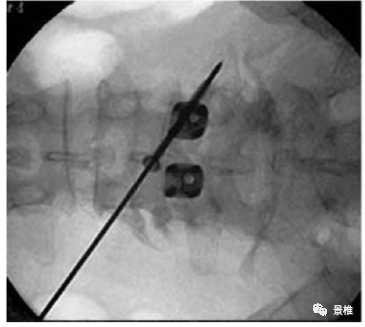

进针点位于棘突根部,指向对侧横突中点与椎弓根外缘交界处。

术中C臂透视正侧位所指向的关键点。